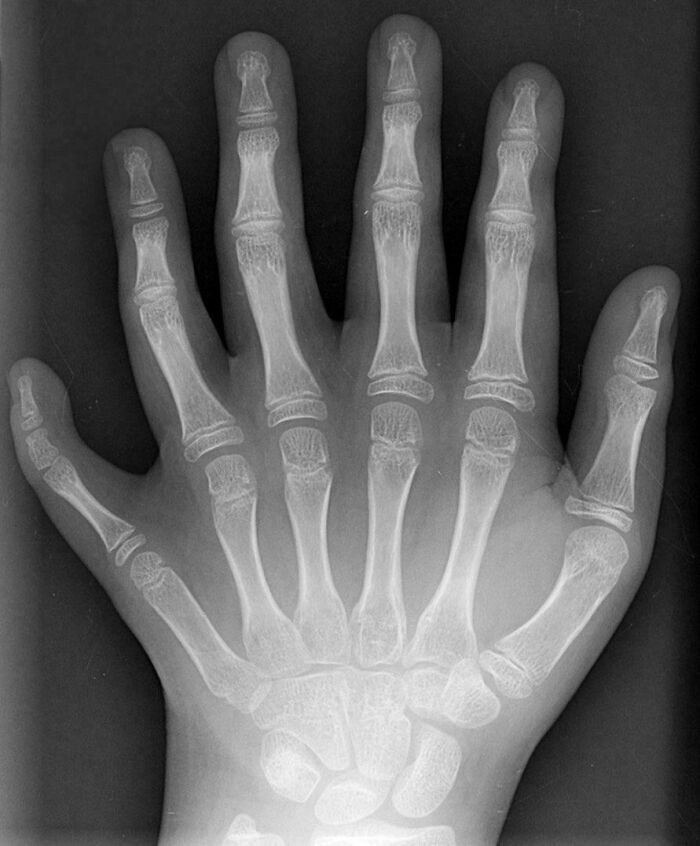

X-Ray Of A Hand With Advanced Rheumatoid Arthiritis

This Condition Is Called Mirror Hand Syndrome, Less Than 100 Cases Have Ever Been Diagnosed And The Cause Is Still Unknown

Genuine question, are all of the fingers usable? Can some medical Panda explain?

An X-Ray Of A Hand With Six Fingers